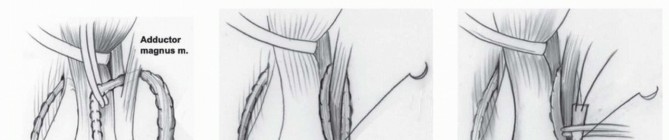

If performed independently, the same midlateral straight incision is used. The anterior and posterior margins of the fascia lata are incised longitudinally. The fascia lata is transected as proximally as possible and reflected distally until its insertion onto the tibia ( TECH FIG 6A ).

The fascia lata is split into two longitudinal strips to make two ligaments. A Krackow whipstitch5 is used to run a nonabsorbable suture from the free end of the fascia lata toward the tubercle of Gerdy in a tubular fashion ( TECH FIG 6B ).

A MacIntosh intra-articular and/or extra-articular ACL reconstruction is performed. The lateral collateral ligament (LCL) is identified. Two tunnels are made. One tunnel is placed under the LCL and does not enter the knee joint ( TECH FIG 7A ). The other tunnel is made subperiosteally, from anterior and proximal to posterior and distal, over the lateral intramuscular septum of the femur ( TECH FIG 7B ). A hole is made in the posterior knee joint capsule by inserting a curved clamp from the “over-the-top” position. The posterior limb of the fascia lata is passed under the LCL. An ACL reamer is used over a guidewire to create a bony tunnel in the proximal tibial epiphysis. The wire is inserted from the anteromedial aspect of the tibia and is directed to the center of the tibial epiphysis. The outer diameter of the actual graft is measured, and the hole in the epiphysis is reamed to this diameter. Illustration 35 for Treatment for Congenital Femoral Deficiency: What You Need to Know Illustration 36 for Treatment for Congenital Femoral Deficiency: What You Need to Know TECH FIG 6 • A. The fascia lata is incised and reflect to Gerdy tubercle. B. The fascia lata is split into two longitudinal strips (FL1 and FL2) to make two ligaments. A Krackow whipstitch is used to run a nonabsorbable suture from the free end of the fascia lata toward the tubercle of Gerdy in a tubular fashion. Illustration 37 for Treatment for Congenital Femoral Deficiency: What You Need to Know Illustration 38 for Treatment for Congenital Femoral Deficiency: What You Need to Know TECH FIG 7 • One strip of the fascia lata (FL1) is tunnelled under the (A) and then under the intramuscular septum of the femur (B). C. FL1 is passed through the intercondylar notch, through the epiphyseal tunnel, and secured with an interference screw. A suture passer is passed through the tibial epiphyseal tunnel and out the posterior capsule of the knee to exit laterally anterior to the septum. The fascia lata suture is pulled through the knee and the bony tunnel using the suture passer. A bioabsorbable headless screw is used to secure the graft to the tunnel ( TECH FIG 7C ). The ACL graft is tensioned and sutured with the knee reduced and in full extension to prevent creation of a fixed flexion deformity of the knee. If only an extra-articular ACL repair is needed, the fascia lata is looped back after passing under the LCL and the lateral intramuscular septum. The fascia lata is sutured to itself and no tunnel is made. To prevent loosening, the graft can be reinforced and retensioned after fixation by passing a nonabsorbable suture anchor through bone at the point at which the graft loops over the intermuscular septum. Illustration 39 for Treatment for Congenital Femoral Deficiency: What You Need to Know Illustration 40 for Treatment for Congenital Femoral Deficiency: What You Need to Know TECH FIG 8 • The second strip of fascia lata (FL2) is tunneled under the patellar ligament, then passed through the intermuscular septum (A), and then sutured back onto itself (B). C. FL1 and FL2 are sutured together, and a bioabsorbable headless screw secures the graft to the tunnel. ## Extra-articular Posterior Cruciate Ligament Reconstruction (Reverse MacIntosh Procedure)9 The anterior skin flap is elevated off the knee and dissected and reflected medially until the entire vastus medialis muscle can be visualized. The anterior limb of the fascia lata is usually not tubularized. It is passed first under the patellar tendon and then through a medial retinacular tunnel ( TECH FIG 8A ). The graft is then passed through a subperiosteal tunnel around the adductor magnus tendon. Finally, it is sutured to itself with nonabsorbable suture ( TECH FIG 8B,C ). This extra-articular ligament is tensioned with the knee in 90 degrees of flexion to prevent an extension contracture. The end of the ACL is sutured to the end of the extra-articular PCL to prevent any slippage.